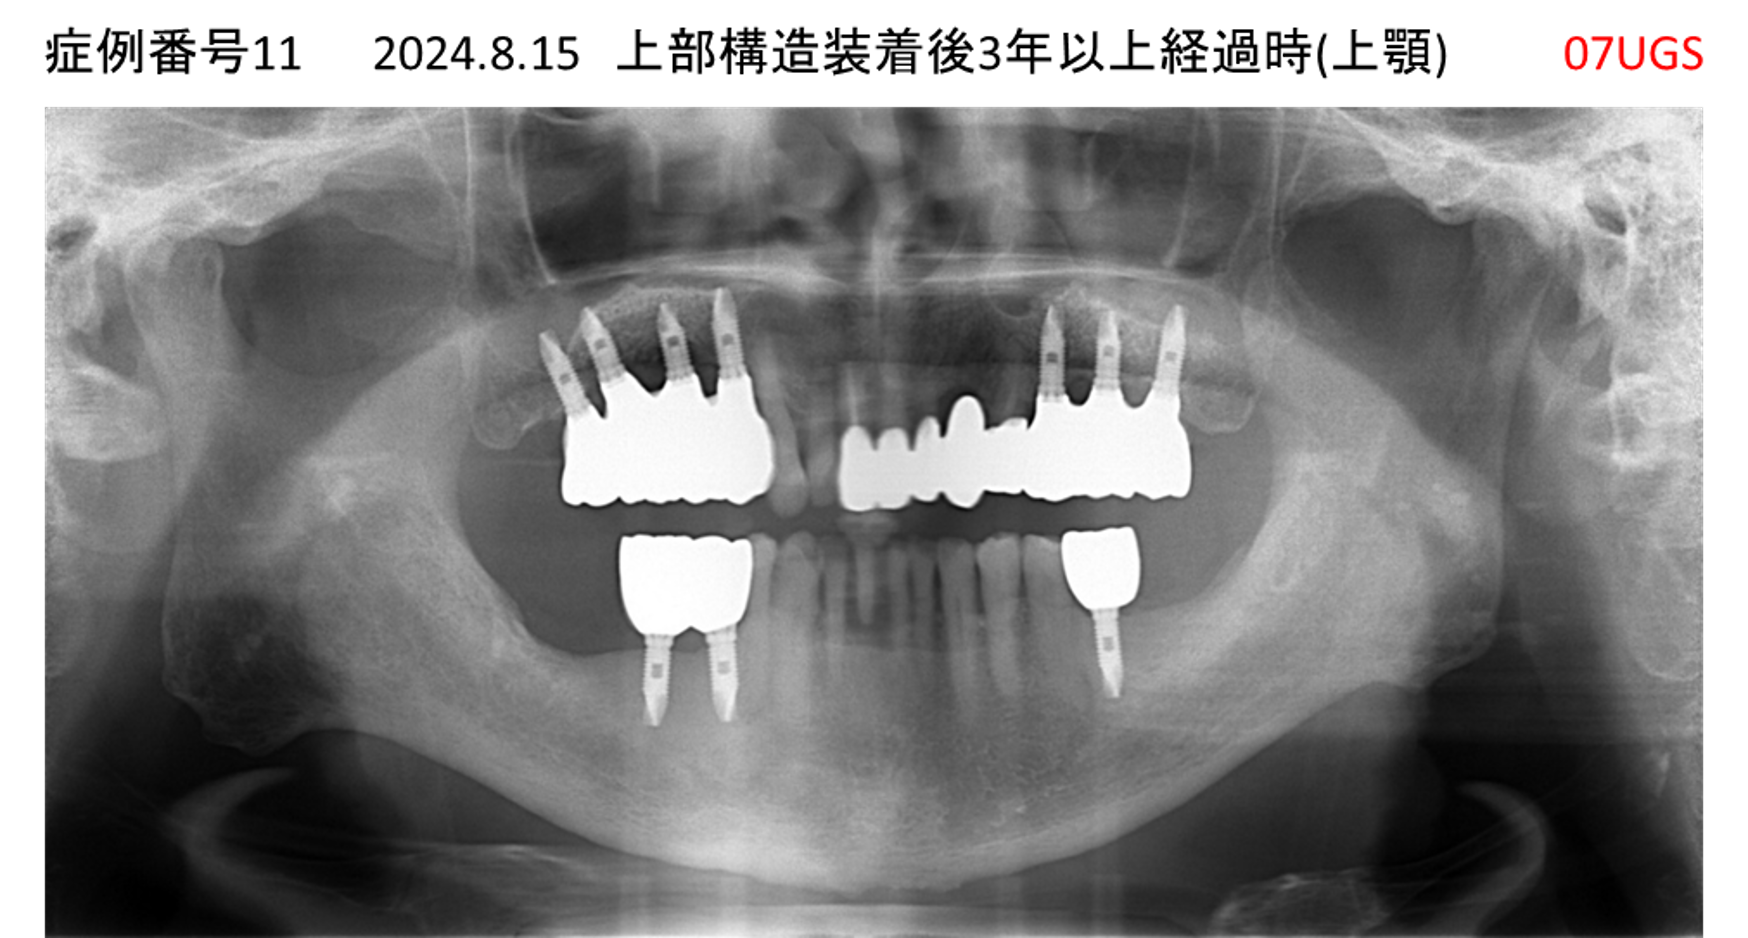

食事ができない/噛めない患者様のインプラント症例

| 治療名称 |

インプラント |

| 治療費用 |

540万円+税 |

| 治療期間 |

6か月 |

| 患者さんの症状(主訴) |

食事ができない。噛めない。上の前歯が揺れてきた。入れ歯がつらい。 |

| 治療内容 |

サイナスリフト、インプラント |

| 治療結果 |

なんでも食べられるようになった。力が入る(全身)ようになった。 |

| 治療の注意点(リスク/副作用) |

インプラントが壊れたら再治療が必要 |